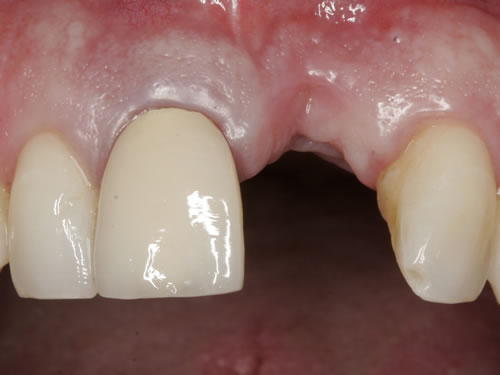

Häufig führt ein Zahnverlust zu einem Verlust von Knochen (Hartgewebe) und der bedeckenden Schleimhaut (Weichgewebe). Besonders im sichtbaren ästhetisch sensiblen Bereich ist es aber notwendig, dass sowohl Hart- als auch Weichgewebe so wiederhergestellt wird, dass im Idealfall das Zahnimplantat mit seiner Krone dem Aussehen des ehemaligen gesunden Zahn entspricht. Als Erfolgskriterien werden aus zahntechnischer Sicht die Form, Farbe und Größe der individuellen Krone angesehen. Aus medizinischer Sicht gibt es wichtige Erfolgskriterien, die die Implantatposition, die Implantatlänge, den Implantatdurchmesser, den Zahnfleischrand im Vergleich zum Nachbarzahn und die Zahnfleischpapillen zwischen den Zähnen beinhalten. Zusätzlich braucht man ein zahntechnisches Labor, das mit der Keramikverarbeitung ein natürliches Aussehen gestalten kann. Nur, wenn alle Parameter perfekt sind, ist das Ergebnis perfekt. Das macht den Einzelzahnersatz im Oberkieferfrontzahngebiet zu einer echten Herausforderung.

Nach der Entfernung von Zähnen kommt es schnell zu Knochenverlust (Resorptionen) und entsprechendem Verlust von Schleimhaut. Die Schleimhaut kann durch bestimmte Operationstechniken wiederhergestellt werden, in dem man freie oder gestielte Bindegewebstransplantate z. B. vom Gaumen entnimmt und das fehlende Material so ersetzt. Das Weichgewebe kann in unterschiedlichen Behandlungsphasen korrigiert werden. In vielen Fällen wird es während der Implantation oder bei der Freilegung verbessert. Manchmal müssen Feinkorrekturen auch nach Eingliederung der fertig gestellten Krone erfolgen, wenn ästhetische Einbußen vorliegen. Häufig hat die Zahnfleischkorrektur auch noch einmal die Änderung der endgültigen Krone zur Folge (Abb. 7.14, 7.15).

Abb. 7.14: Unbefriedigendes ästhetisches Ergebnis nach Implantatversorgung.

Abb. 7.15: Perfektes Ergebnis nach Weichgewebskorrektur und nach Eingliederung der geänderten Krone.